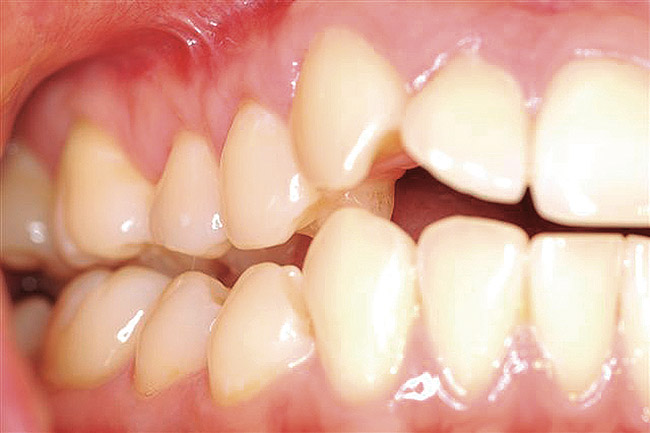

The patient presented with gingival recession and a complaint of cold sensitivity in the maxillary first and second bicuspid teeth (Figure 14). Minimal attached gingiva was noted. A connective tissue graft was placed to widen the band of attached gingiva and eliminate the cold sensitivity present presurgically (Figure 15).

Figure 14  Gingival recession on the first and second maxillary premolars with a thin band of attached gingiva.

Figure 14

Figure 15   Correction of the attached gingiva and repair of the recession shown 8 weeks postsurgery.

Figure 15